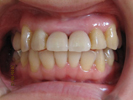

50代女性

歯がこのままではダメだと思い、一念発起された50代女性の方です。

もちろん治療期間が長期にかかることも、治療費が高額になることも、外科的な手術が何度か必要であることなど、

インプラント治療と咬み合わせ治療のほぼ全てを大名歯科ホームページで予め知っていただいた上で決心され来院されたそうです。

インプラント治療は顎骨が乏しかったため、増骨手術も併用しなければならない難症例でした。

治療期間中は残存歯数が少ない上に、丈夫でないため生活に不自由な点がでました。

さらに咬み合わせが安定しにくい症例のため、プラスチック仮歯がよく壊れたり、外れたりして、修理に来院していただくなど大変な苦労とご迷惑をおかけしました。

審美性(見た目)は十分回復できたと思っており、患者さんも大変満足されています。

食事は当然のことかもしれませんが、よく咬めるようになったそうです。

咬み合わせ治療は非常に難しいため、これで十分かどうか分かりませんが現在もこのまま定期的なメインテナンス中です。